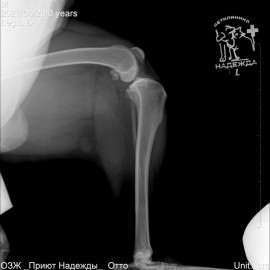

Собака породы хаски. Обратились с жалобами на хромоту на заднюю левую лапу. Были проведены исследования в ходе которых был поставлен диагноз: остеоартрит левого коленного сустава, разрыв передней крестообразной связки левого коленного сустава. Была проведена операция - TPLO.

Снимок 2 после операции